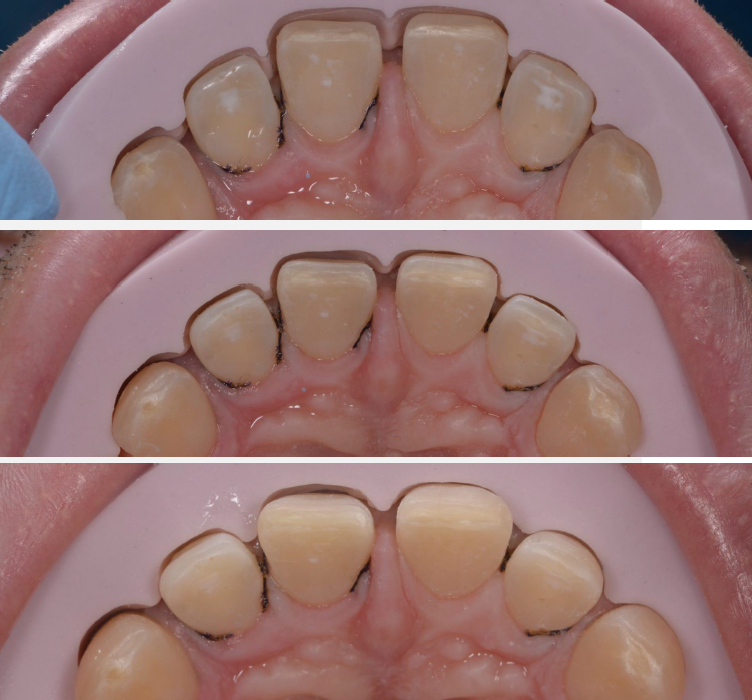

A close-up of teeth sowing the upper jaw and a ping material

Preparation guide fabricated on the final wax-up was used to control the space needed for ceramic veneers: view before and after the minimal preparation of incisal and interpoximal areas.

3 teeth close-ups combined in one image. Showing the upper jaw from underneith and pink paste

Minimal preparation of the buccal surfaces with segmented guide fabricated on the final wax-up: checking reduction at the incisal edge, in the middle, and at the soft tissue level.